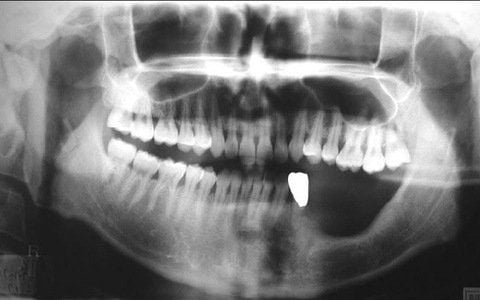

Một tác dụng phụ nghiêm trọng của bisphosphonates và denosumab là phá hủy hàm, còn được gọi là hoại tử xương hàm (osteonecrosis of the jaw-ONJ). Hầu hết bệnh nhân sẽ cần phải được sự chấp thuận từ nha sĩ trước khi sử dụng một trong những loại thuốc này.